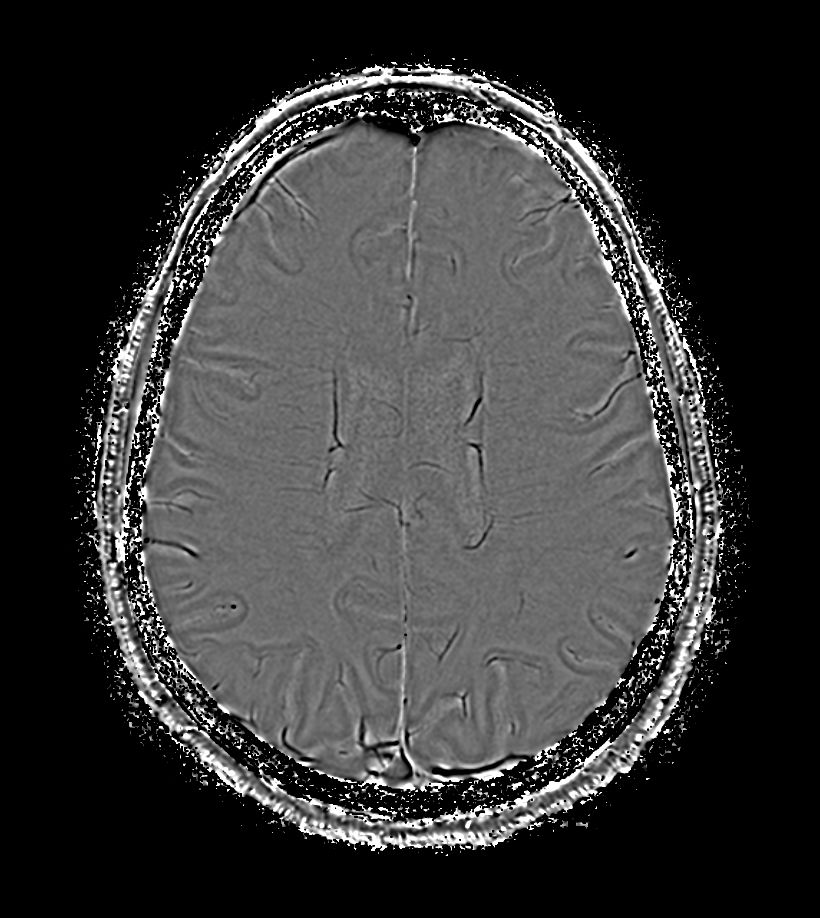

3D T1w FFE Compressed SENSE